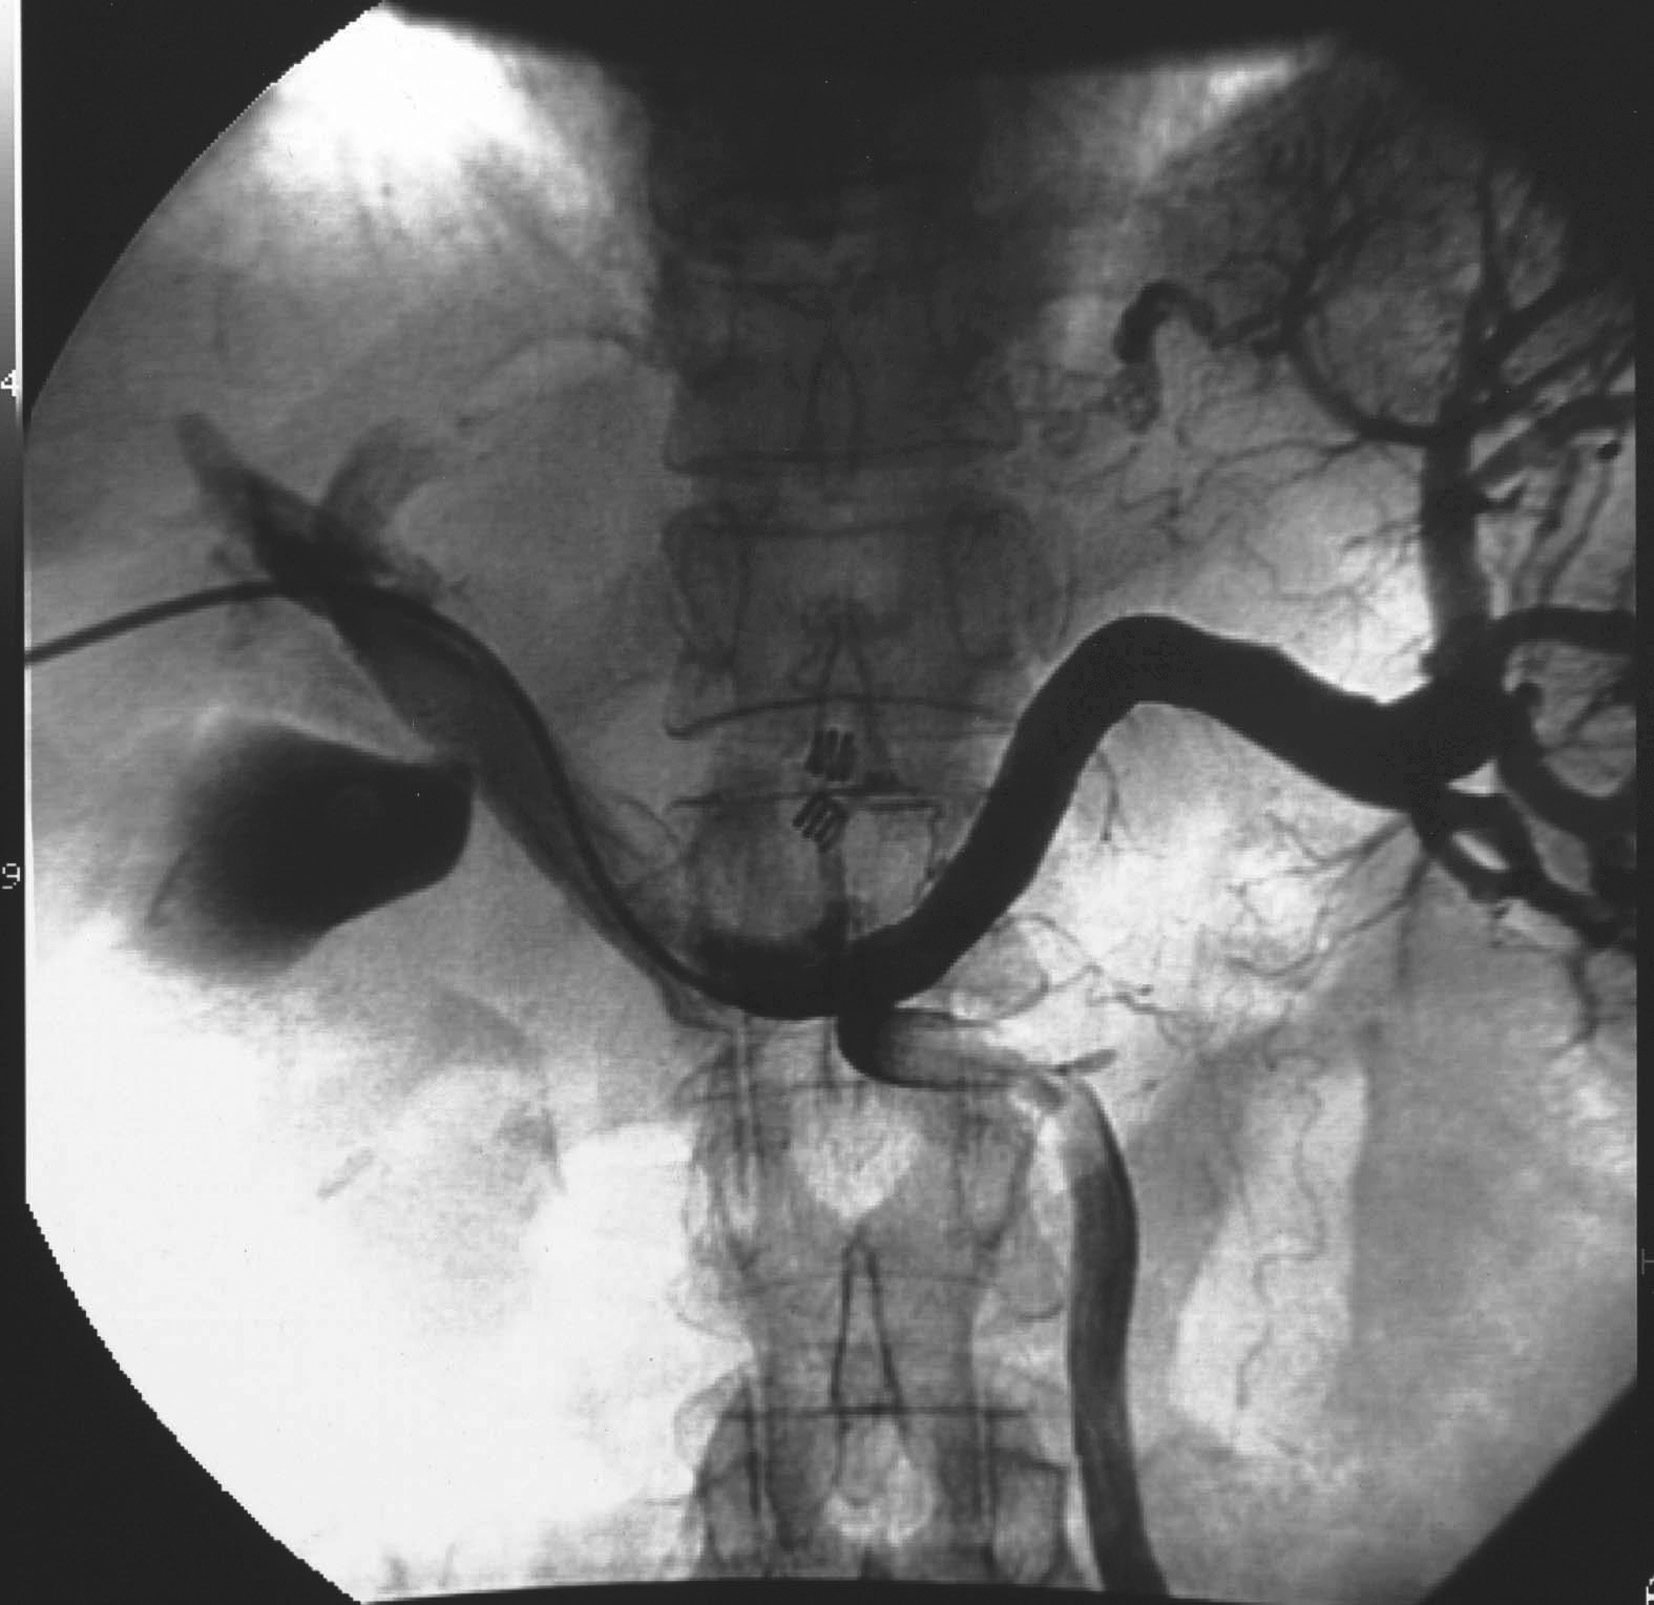

对比剂进入并显示门脉系统的形态分布,包括:门脉属支(肠系膜上、下静脉和脾静脉及其分支)、门脉干和门脉的分支(门脉左支和右支及其分支),同时可以观察门脉血流动力学状况。门脉造影可以为门脉相关疾病的诊断提供依据,也为经门脉的治疗提供解剖学基础和途径。根据对比剂进入门脉的方法不同,可有以下3种途径:

间接门脉造影即插管入脾动脉和/或肠系膜上动脉后,注入4~5mL/s,总量25~30mL造影剂,延长观察时间,不仅观察动脉期和实质期,还要观察对比剂回流后显示的门静脉期(图5-21-51)。间接门脉造影的操作相对简单,但通过对比剂的回流显示门脉,可受门脉循环时间和对比剂量的影响,且无法用来测量门脉压力。

图5-21-51 经肠系膜上动脉间接门脉造影

A.插管入肠系膜上动脉注入造影剂;B.经肠系膜上静脉回流后,可显示肠系膜上静脉、门脉干和门脉的分支

直接门脉造影即通过穿刺插管进入门脉的属支或门脉干,然后注入对比剂,造影观察门脉系统的情况和门脉血流动力学,可作为诊断门脉病变的“金标准”,也可作为门脉系统病变的治疗途径。其入路有:①经皮肝途径。多首选经右腋中线附近,采用21~22g的穿刺针穿刺门脉的右支及其2~3级分支,成功后引入导管进入门脉干。困难时,亦可选择经剑突下穿刺门脉左支及其分支(图5-21-52)。②经左腋中线附近采用21~22g的穿刺针穿刺脾静脉分支,然后插管进入门脉干(图5-21-53)。③经颈静脉,采用特殊的穿刺针经肝静脉穿刺肝内门脉分支[transjugular intrahepatic portosystemic stent-shunt(TIPSS)途径,图5-21-54]。④其他少用途径。如通过外科手术的方法,分离出肠系膜上静脉的分支,然后直视下插管入门脉等。常用的是经皮肝入路。穿刺可以在超声或(结合)透视引导下完成。门脉插管成功后,可注入适量的对比剂,行门脉DSA,显示门脉的情况,同时可经导管测量门脉的压力。采用导管导丝技术,可行超选择性插管进入门脉的属支或者门脉的分支内,同时可造影和测压。本法虽有一定的创伤,但是诊断门脉病变的“金标准”。其适应证为:①观察门脉系统,包括:门脉属支、门脉干及其分支血管的病变和解剖变异,如门静脉瘤、门静脉狭窄或闭塞、门静脉侧支循环的开放和门静脉海绵样变等。②为门静脉高压的诊断提供证据。测量门静脉压力持续升高(>10mmHg),即为门静脉高压。③为经门静脉的治疗建立了途径。如肝恶性肿瘤区域门静脉的栓塞以促进正常肝的代偿,出血门静脉分支的栓塞,建立肝内门静脉和腔静脉的分流道(TIPSS)以降低门脉压等。其禁忌证是相对的,主要是出凝血功能严重障碍和肾功能衰竭。门脉系统慢性完全性闭塞并血管成条索状改变,可能导致门脉穿刺插管失败。本法的并发症主要来源于穿刺插管途径的损伤造成的出血,栓塞造成的门脉血栓形成等。采用有效的方法准确的栓塞肝内的穿刺入路,可减少出血的发生,如用明胶海绵条、钢圈和组织胶等。穿刺过程中损伤肝动脉的分支亦是术后出血的原因之一,必要时行肝动脉造影明确和行栓塞术。